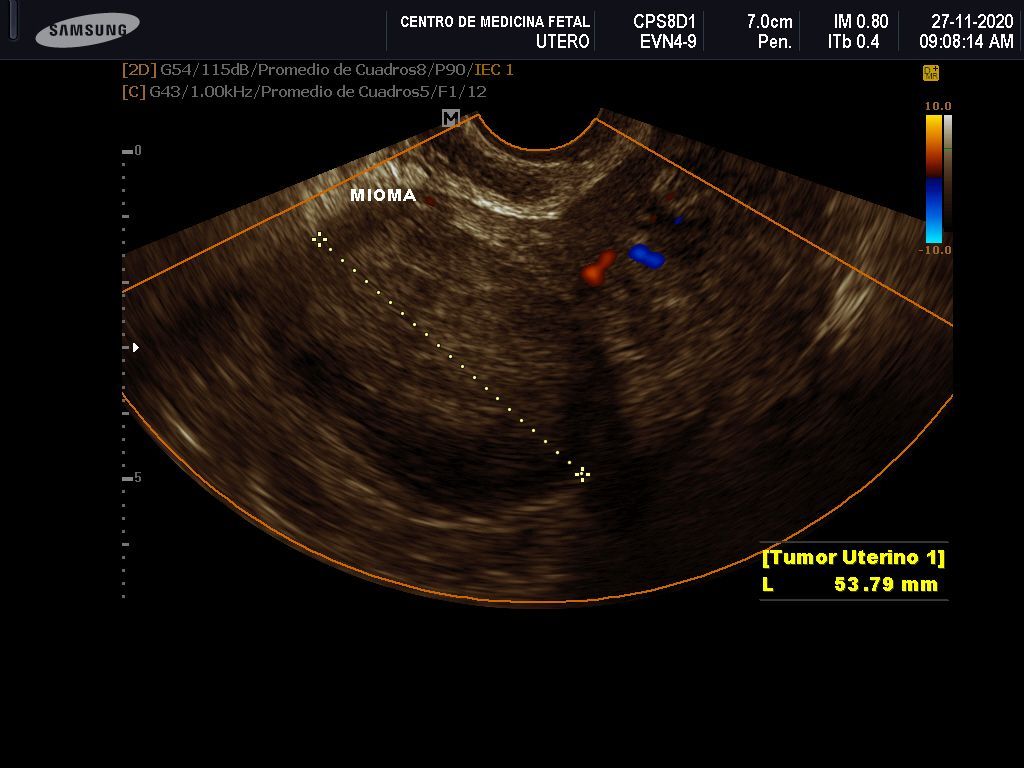

- Detección ecográfica transvaginal o pélvica y tratamiento de: Miomas, quistes de ovario, endometriosis, malformaciones uterinas